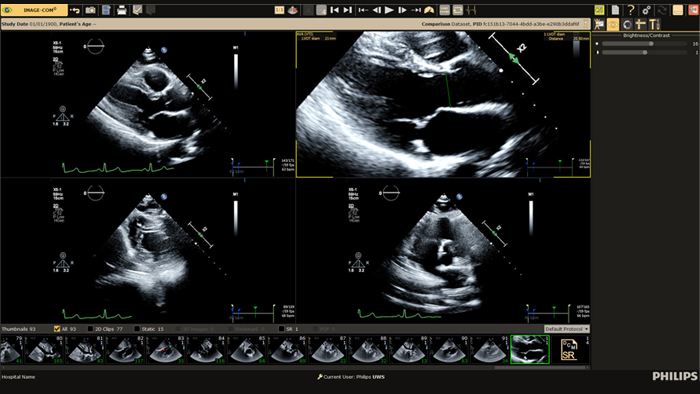

Wir zeigen, wie Bildgebungstechnologien durch ausgezeichnete Qualität bei der diagnostischen Bildgebung, mittels Analysen, Berichterstellung und durch Einblicke über verschiedene Bildgebungsmodalitäten hinweg lebensverändernde klinische Erkenntnisse für Patienten und kardiologische Behandlungsteams bieten. Dabei unterstützen sie gleichzeitig die Arbeitsabläufe, Effizienz und Zufriedenheit der Mitarbeiter.

Prüfen, analysieren und quantifizieren Sie klinische Daten von verschiedenen Modalitäten und für unterschiedliche klinische Indikationen mit KI-gestützten 3D-Modellen, Kartendarstellungen und anderen Quantifizierungsfunktionen.

Stellen Sie einen einzigen Zugriffspunkt für die kardiovaskulären Diagnosefunktionen und Bilder mehrerer Modalitäten des Patienten in voller diagnostischer Qualität zur Verfügung, einschließlich vorheriger Untersuchungen, Befunde, Messungen und Berichte.

Ermöglicht eine höhere Effizienz bei der Ansicht, Analyse und Berichterstellung, indem es Behandlungsteams die Flexibilität gibt, je nach aktuellen und zukünftigen Anforderungen unterschiedliche Arbeitsabläufe anzuwenden.